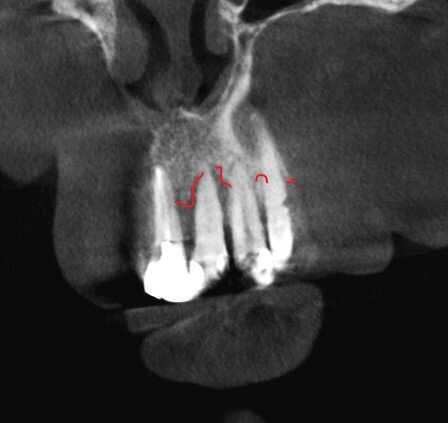

Вот почему зубы нужно удалять:

Зубы обозначены номерами без привязки к классификации.

1 - объёмная вкладка, которой очень много лет. Постоянно выпадает, от стенок зуба ничего толкового не осталось.

2 - корень, от которого ничего не осталось и он не пригоден для восстановления.

3 - зуб выдвинулся, наклонился. Имплантату с коронкой этот зуб будет мешать, не получится адекватной гигиены и велики риски потерять конструкцию. Но пациент не готов к расставанию. Не настаиваем.

4 - кариес корня в таком объёме и в такой локации, что шансов у зуба не остаётся.

Стоматологи, консультировавшие пациента до, проблемы не видят и предлагают 2 варианта:

1. Удаление и одномоментная имплантация.

2. Удаление, ожидание, имплантация.

Всё с синус-лифтингами, насколько память не изменяет. Но не суть.

Что же нас смутило?

Поэтому, как только такие зубы будут удалены, зоны роста вернутся к естественному, природному положению - "встанут" ровно, плюс подвергнутся неминуемым процессам деструкции.

Как тогда ставить имплантаты? Хорошего ничего не будет. Одномоментно имплантировать? Зонам роста плевать, при удалении зуба останется "дырка" в кости, стенки костной лунки (кортикальные пластинки) будут слабы и зоны роста "уедут" - ничего их не остановит.

Поэтому план такой - НИКАКОГО МАССОВОГО удаления зубов:

1. Удаление зуба под номером 1 и консервация лунки. Ждём 4 месяца.

2. Удаление зуба под номером 2 и пластика собственной костью, взятой с бугра в/ч. Ждём приживления 4 месяца.

Зуб под номером 4 не столь интересен и время его удаления не буду расписывать. Как решит хирург, так и будет.

Таким образом мы сохраним максимально возможное количество кости. Ничего лучше, увы, не придумаешь.